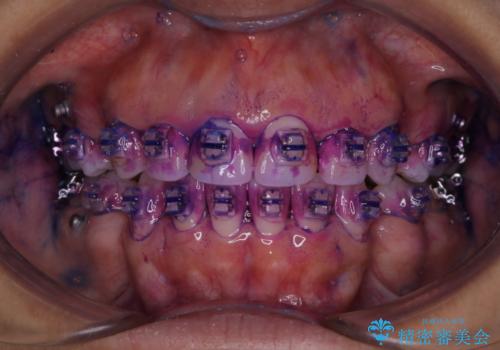

- 歯科がかなり久しぶりで、今後虫歯治療予定のためまずはクリーニングを希望されました。PMTC60分コースを行いました。

歯の表面に、茶色く色が残っている所がありますが、これは詰め物の変色の所と、虫歯になっている所です。以前に、CR(コンポジットレジン)による虫歯治療がされています。

CRは経年的劣化や、着色してしまうことがあります。PMTCでクリーニングを行うと、古いCRが目立つことがあるため、気になる際は詰め替えを行います。

茶色くなっている部分が、着色なのか、劣化なのか、虫歯によるものなのかは判別が難しいことがあります。そのため、定期的にPMTCを行うことで状態の確認が的確に行えます。

また、治療が開始される前などにも、全体的にクリーニングを行いご自身本来の歯の色、状態を精密に確認することが大切です。